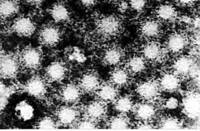

(一)形態與結構病毒呈球形,直徑約為27nm。無囊膜。衣殼由60個殼微粒組成,呈20面體立體對稱,有HAV的特異性抗原(HAVAg),每一殼微粒由4種不同的多肽即VP1、VP2、VP3和VP4所組成。